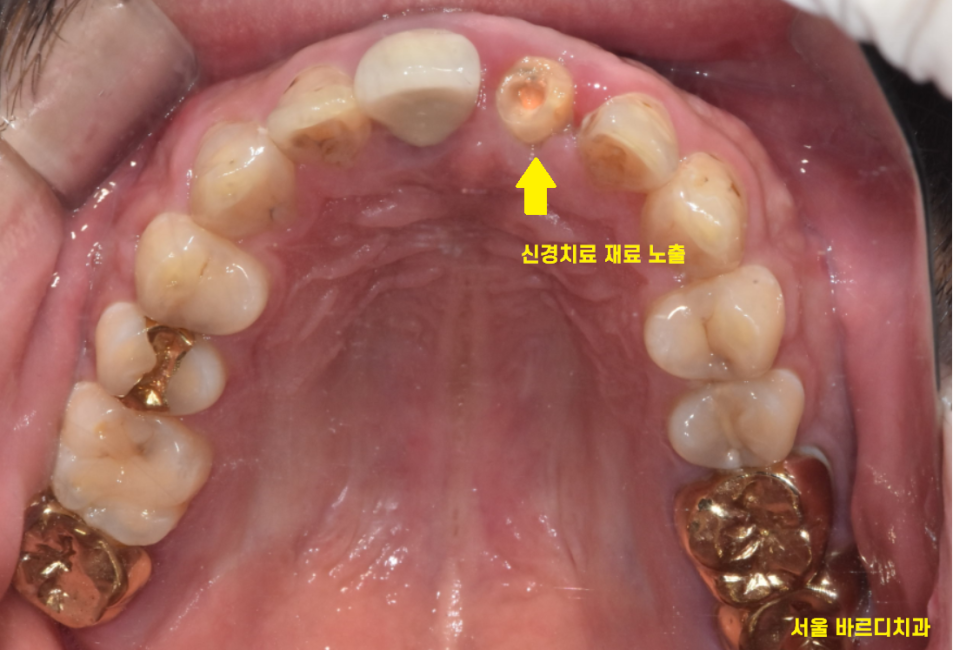

큰 x-ray로 확인을 해보니..

여지없이 신경치료가 되어 있는 상황

23.12.26

작은 x-ray로 한 번 더 확인해 보았습니다.

2/3 이상 머리가 없어졌네요..

앞니 부러짐 치료의 방향을 결정할 때에는

남아있는 치아의 양이 중요합니다.

살릴 수 있을지 없을지

예후를 결정하는

key point이죠!!

잇몸뼈에 뿌리만 박혀있는 수준이라

발치 후 임플란트 계획을

잡아드렸습니다.